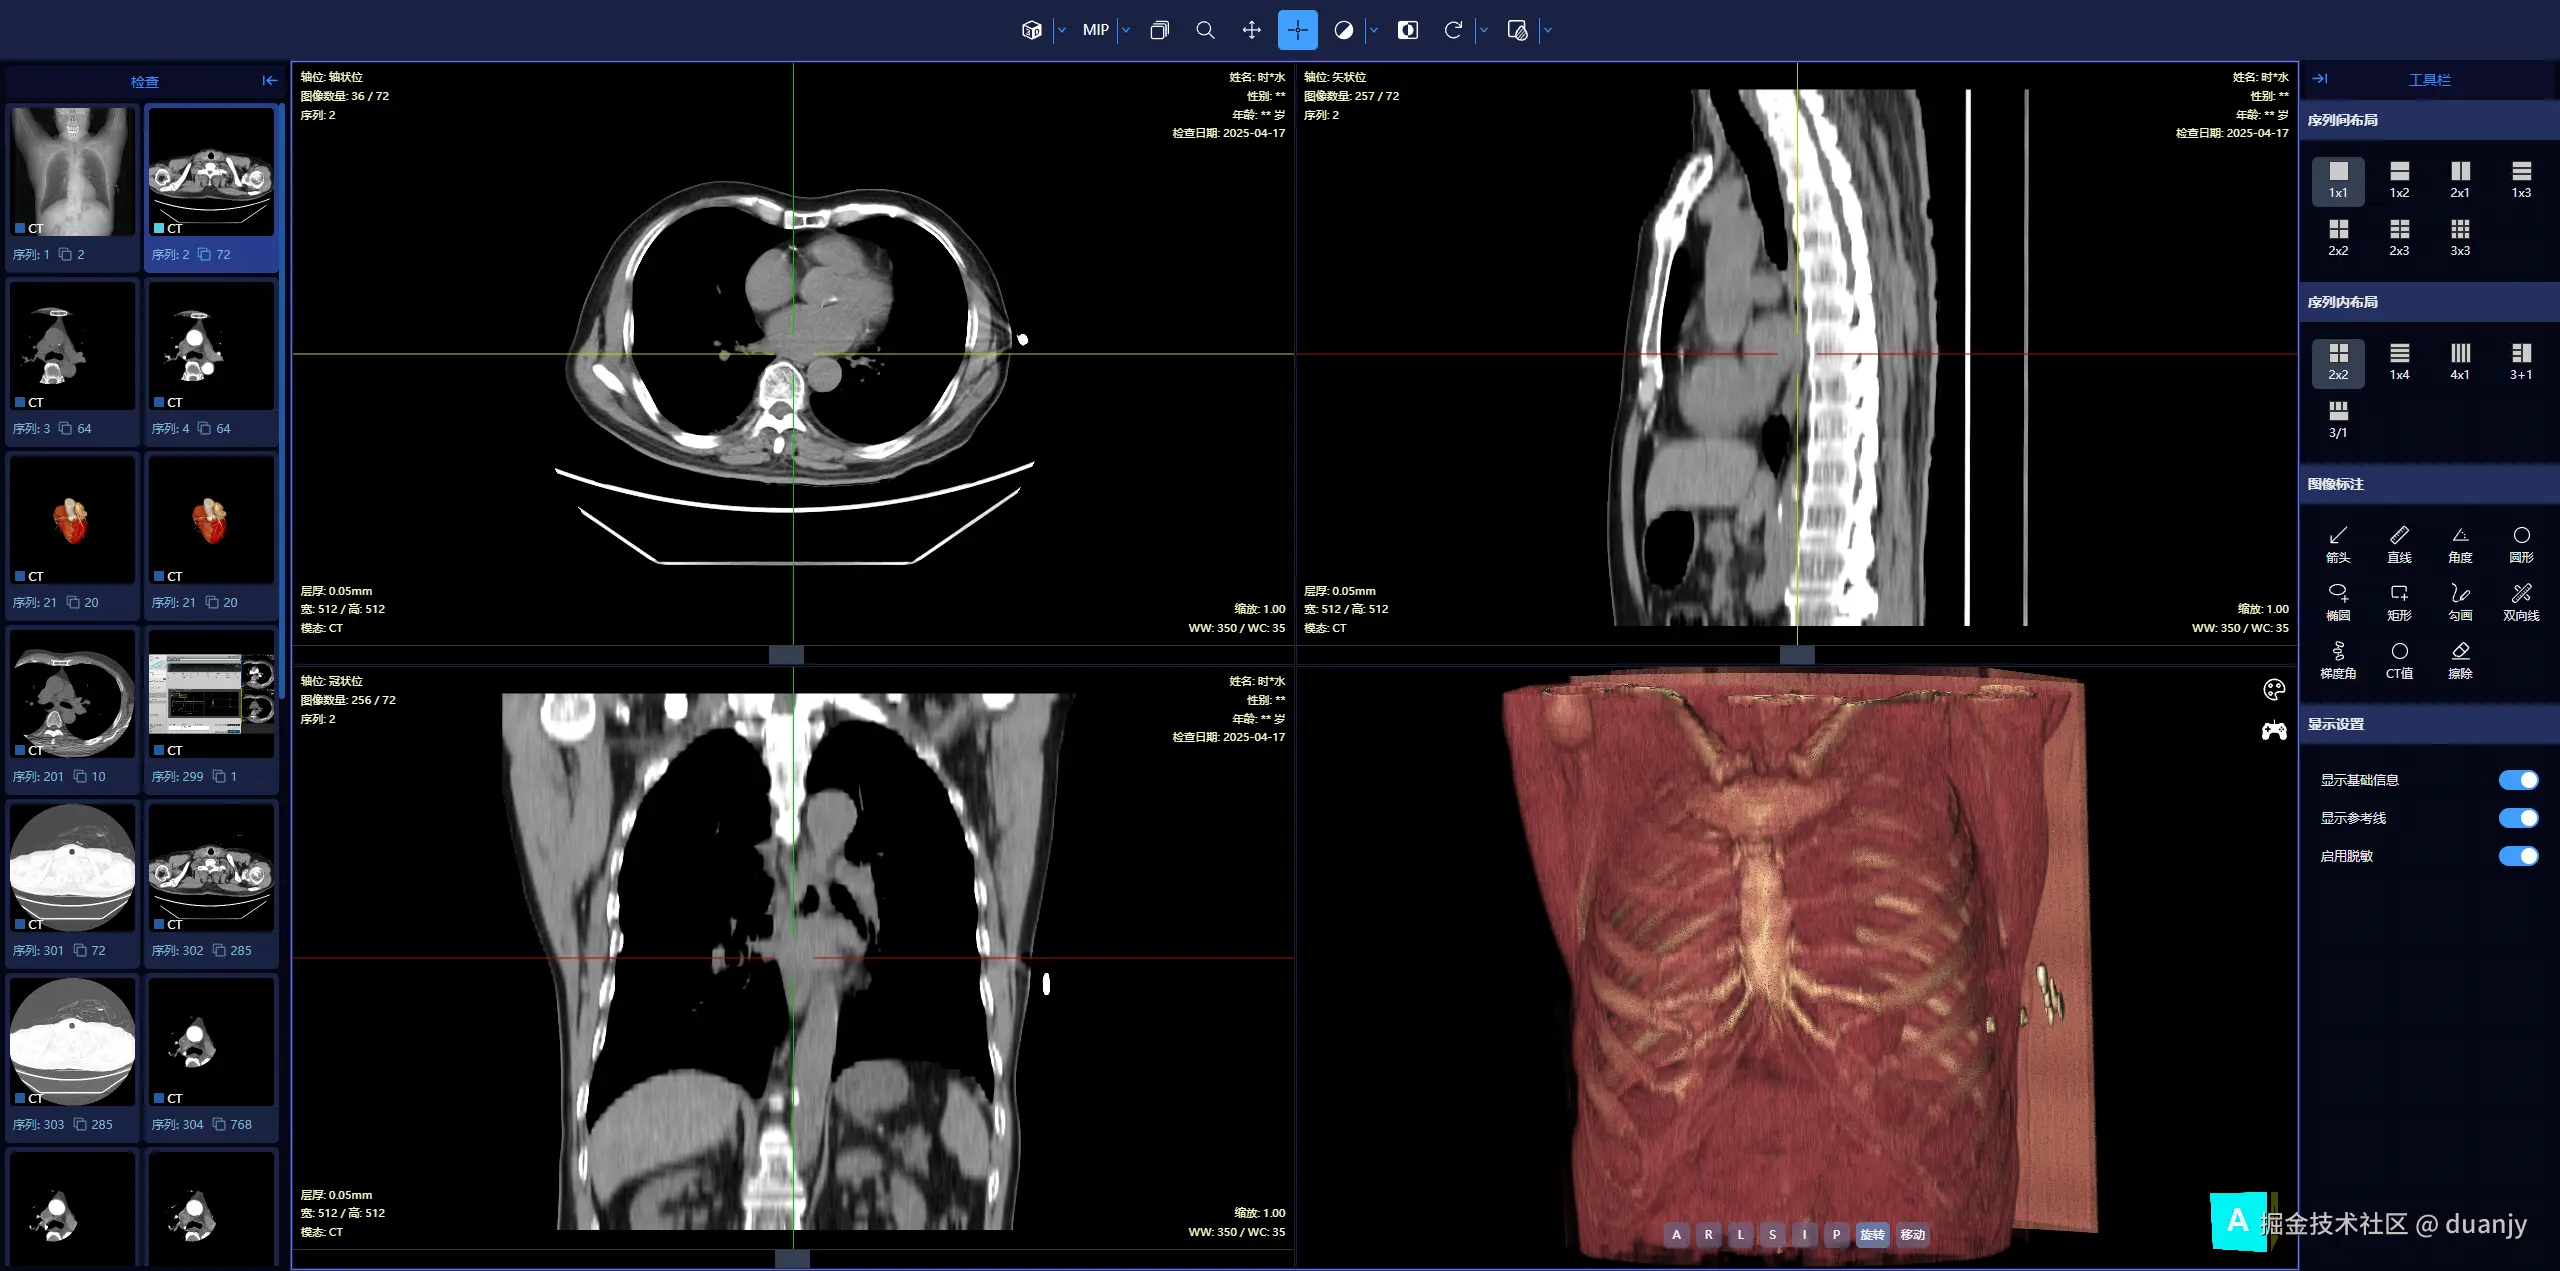

1. PC端 – 三维重建

screenshot-3d.png